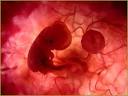

Desenvolvimento embrionário humano

O desenvolvimento humano inicia-se na fertilização, quando um espermatozóide se une a um ovócito para formar uma única célula: o zigot. É a partir desta célula totipotente que o indivíduo se desenvolve. O zigoto, visível a olho nu é como um pequeno grão, pouco menor que o ponto final desta frase. Contém os cromossomas e os genes derivados da mãe e do pa. O zigoto unicelular divide-se muitas vezes e transforma-se, progressivamente, em um ser humano multicelular, através de divisão, migração, crescimento e diferenciação das células.

A embriologia é a ciência que estuda a formação dos complexos órgãose sistemasde um animal , a partir de uma única célula indiferenciada. Faz parte da biologia do desenvolvimento. Considerando-se o desenvolvimento humano, este desenvolvimento inicia-se pela fecundação, gerando o zigoto ou ovo, que passará por três fases sucessivamente: mórula, blástula e gastru